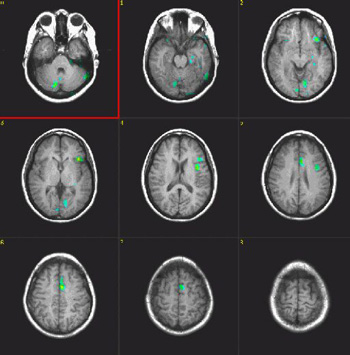

| Activación |

Se muestra el área de Broca y el área motora suplementaria (AMS) izquierda. Aparece algo de activación en la formación hipocámpica izquierda y las áreas visuales. Esta última activación podría explicarse como el efecto de imaginar los objetos a los que se hizo referencia en la condición "ACTIVADO". También se produce activación en el cerebelo derecho y en la circunvolución temporal inferior izquierda.